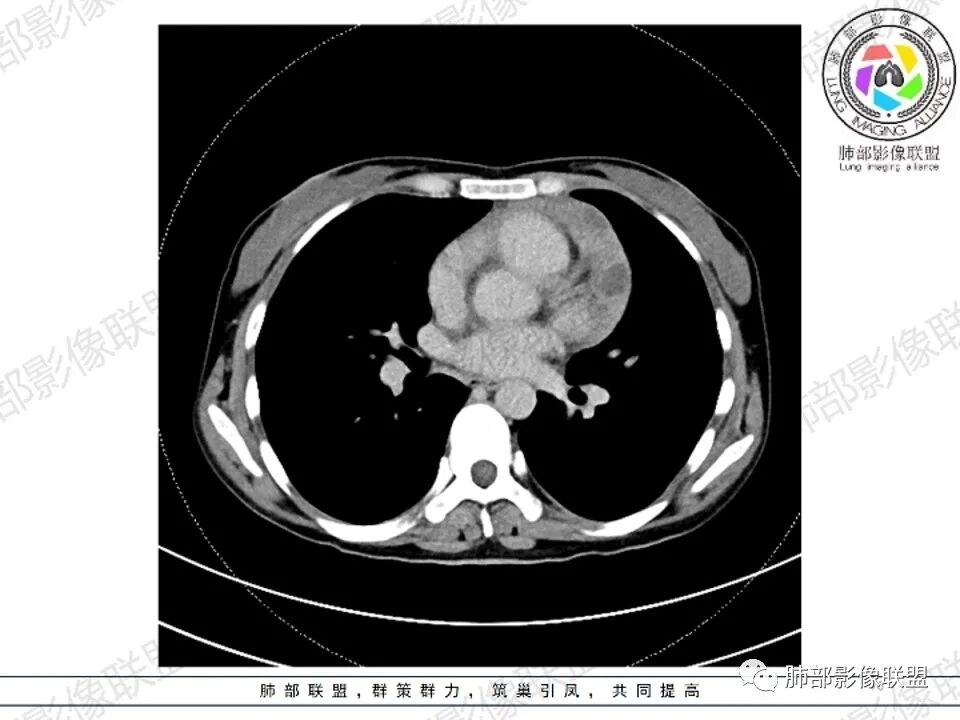

女,27,间断头晕、乏力3年,左眼视物模糊2月。贫血。胸部CT:前纵隔不规则肿块,多结节融合,边界不清,沿主动脉及肺动脉间隙生长,平扫密度欠均匀,增强扫描可见多发低密度坏死,纵隔血管供血穿行,腋窝多发大小不等淋巴结肿大。考虑恶性病变,胸腺癌?肉瘤?淋巴瘤?鉴别胸腺瘤、结节病等。

临床:年轻女性,慢性病程,多系统病变,头晕,贫血,视物模糊。

CT:定位纵膈病变,前中纵隔多发肿块,质软,塑形,密度不均匀,边界清楚。增强不均匀强化,坏死边界清楚,血管漂浮征。双侧腋下多组淋巴结肿大,明显异常强化。

2.影像显示前纵隔不规则块状影,依势贴附心脏大血管旁,密度不均,边界不甚清楚,有结节融合感。

3.病灶轻度不均匀强化,可见血管穿行,散在液性低密度区。

双肺门未见肿大淋巴结。

1.年轻女性,前纵隔不规则块状影,密度不均,边界不甚清楚,有结节融合感,轻度不均匀强化,可见血管穿行,最常见最符合的无疑是淋巴瘤!